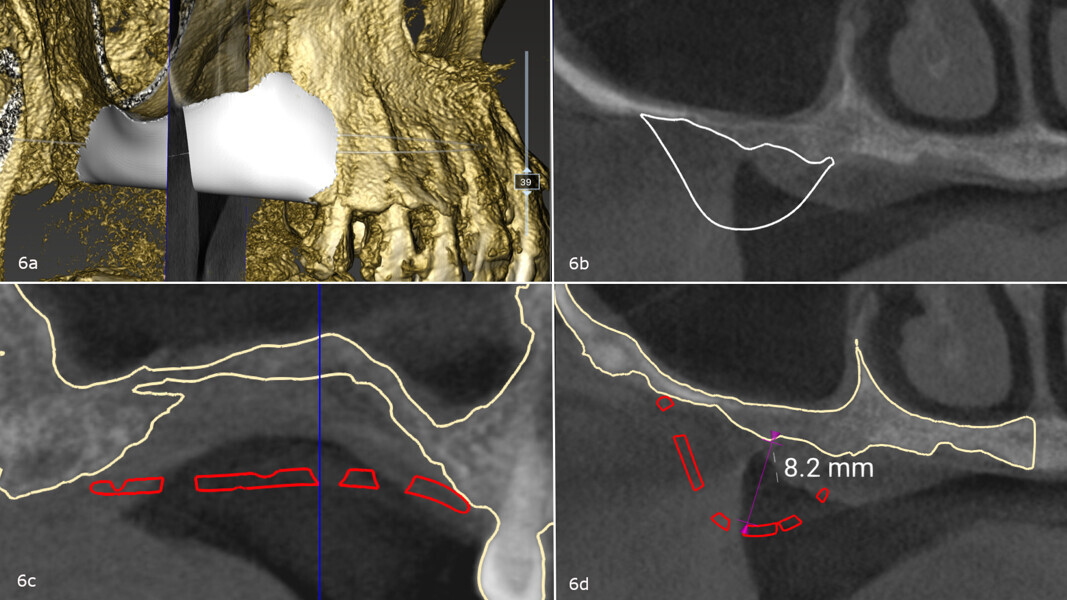

The treatment plan was developed using a fully digital workflow. The DICOM files obtained from the preoperative CBCT scan were used to generate a 3D reconstruction of the maxilla, which allowed for the virtual design of the ideal bone volume for the placement of three implants in sites #15, 16 and 17 (Figs. 6a-d; 7a & b). Subsequently, the customised mesh corresponding to the increased volume in the patient’s maxilla was created virtually (Figs. 8a-f).